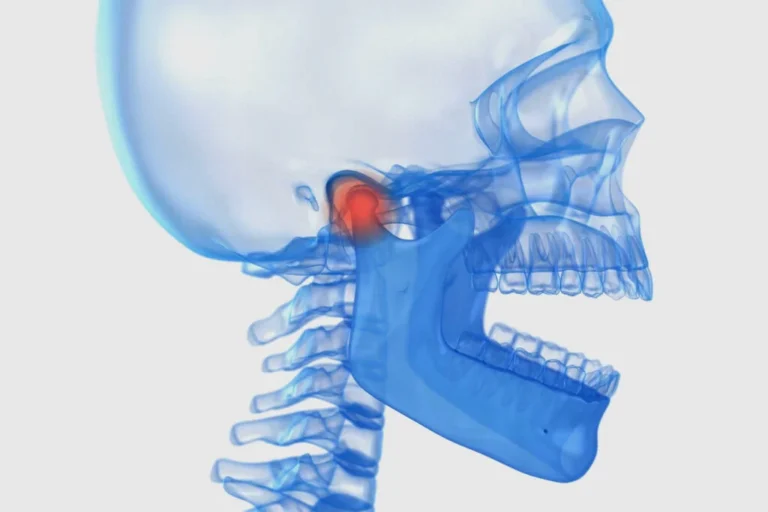

Czym jest elektrokoagulacja? Elektrokoagulacja to zabieg polegający na kontrolowanym wykorzystaniu prądu elektrycznego w celu zamknięcia naczyń krwionośnych oraz usunięcia zmienionych tkanek. W stomatologii metoda ta znajduje zastosowanie przede wszystkim w chirurgii i periodontologii. Stomatolog w nowoczesnej klinika stomatologiczna Kraków wykorzystuje…